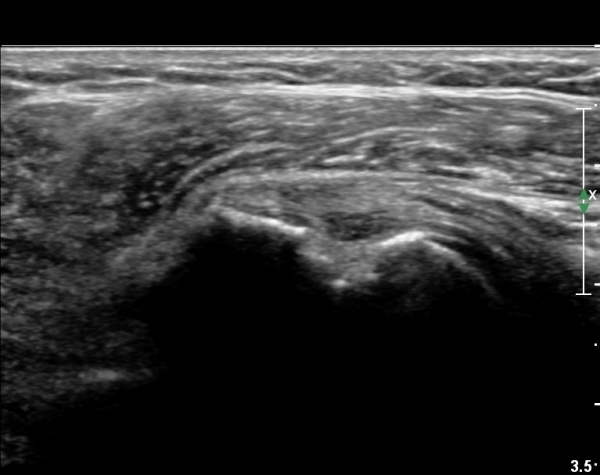

ŽÃËÀÚ¸¦ Á¶±Ý ¾Æ·¡·Î À̵¿ÇÏ¿© À̵ιڱٰÇÀÇ È¾´Ü¸é°Ë»ç¿¡¼­ ÀÌµÎ¹Ú±Ù°Ç ÁÖÀ§ ¼ö¾×Àú·ù°¡ °üÂûµÈ´Ù(»çÁø 3, 4).

À̴ Ȱ¾×¸·¿°Áõ ¼Ò°ßÀ¸·Î Ãæµ¹ÁõÈıº ¶Ç´Â ȸÀü±Ù°³ ÆÄ¿­ ½Ã ÈçÈ÷ °üÂûµÇ´Â

¼Ò°ßÀÌ´Ù.